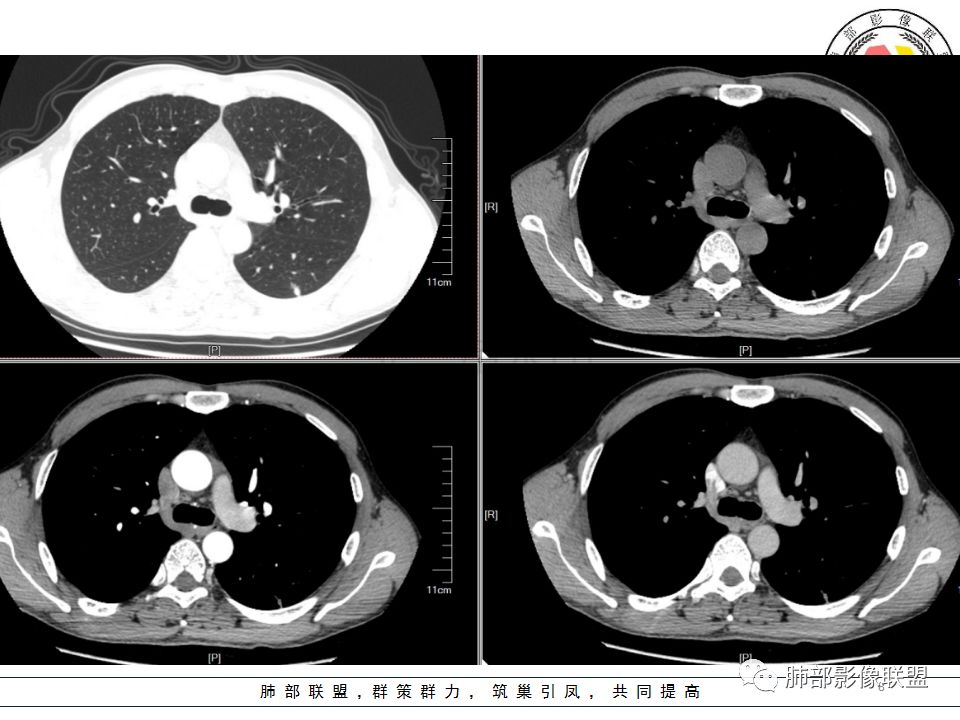

左肺下叶背结节丶融合趋势,形态较单一,平直,无胸膜凹陷,目测轻强化,有支气管爬行丶子灶。诊断:TB>pC>腺癌。

左肺下叶结节,边缘平直为主,部分膨隆,卫星病灶,似乎无强化,糊墙,胸膜下脂肪间隙增宽,结核可能性大,腺癌待排。

左肺下叶背段孤立结节,长轴与胸膜平行,支气管近端截断,刀削平直,糊墙,卫星灶轻强化,考虑TB。

左肺下叶背段小结节 ,糊墙 ,胸膜外脂肪间隙增宽 ,引流支气管壁厚 ,有爬行征 ,病灶无明显强化,考虑结核可能。

考虑结核,左肺下叶病灶,强化不明显,胸膜反应性增厚,有卫星灶,强化不明显。

病史:男,50岁,胸痛15天,无抽烟;胸膜下病灶,有可能相关;

影像:病灶不规则,形态奇特,矢状位可能看到病灶的真实形态;上面近端病灶似乎与主病灶不相连续,多病灶?内侧似乎小花小草,疑为卫星灶;胸膜下病变,与胸膜关系不密切,胸膜线状强化;强化方式渐进性,感觉不均匀,也许是伪影;病灶凹陷平直不膨隆,考虑良性。诊断:结核;鉴别:腺癌(近胸膜端三个胸膜反应凹,偏上部层面毛刺不能除外,但其他地方没有,整体收缩力还比较弱,无钙化,考虑没有形成钙化和纤维化。

男性,胸疼,左肺下叶背段结节,边缘光滑,有平直收缩,轻度延迟强化?胸膜肥厚,有轻度胸膜牵拉,周围有卫星灶,考虑炎性病变,结核,隐球可能性大。鉴别腺癌。

左肺下叶背段结节,边缘较光整,平直,近端支气管未见明确截断征象,沿支气管走行,临近胸膜局限性增厚,增强目测未见明确强化,周围见稀疏小树芽分布,整体考虑良性病变,结核放前考虑。

男,50岁,左肺下叶结节影,似乎两个结节,相邻,上面一个偏内,有分叶,下面一个偏外,胸膜下,内侧有稍增厚的支气管影,并且支气管进入病灶内,周围有更小卫星灶,外侧有胸膜增厚,糊墙。总的来说,考虑炎性病灶,结核可能性最大。但靠内侧的结节有恶性特征,腺癌待排。

50岁男性,吸烟,胸痛15天。左肺下叶胸膜下结节,边缘平直为主,部分膨隆,但似乎呈山丘,沿支气管爬行,周围是卫星灶还是小花小草,考虑恶性,小细胞癌可能性大,结核待排。

左肺下叶背段结节,边缘光滑,有平直收缩,强化不明显,胸膜肥厚,有轻度胸膜牵拉,周围有卫星灶,考虑感染性病变,结核首选。

左肺下叶背段结节,形态近似两个结节融合或靠近,沿支气管走行分布,近侧支气管内见条状软组织,增强未见明确强化,周围见小树芽,首先考虑结核,鉴别小。

患者中年男性,因胸痛半月入院。查血常规、凝血功能、肾功能正常。有抽烟史。胸部CT:左肺下叶背段胸膜下与胸膜垂直长条形不规则病灶,支气管爬行改变,边缘欠清楚,部分层面呈葫芦样见血管集束征、周围点状卫星灶,增强无明显强化,左肺门淋巴结肿大。综合常规结核可能性大,其次小细胞肺癌。鉴别其他。

左肺下叶病变,边缘平直,似有U形凹陷,树芽及卫星病灶,支气管爬行征?无明显强化,考虑结核。

左肺下叶背段近胸膜下结节,部分边缘平直并可见卫星灶,增强后强化不明显,首先考虑结核。

中年男性,左肺下叶背段结节,内可见支气管充气征,周围有晕,周围有结节,局部胸膜增厚,可见脂肪间隙。考虑良性病变可能,隐球?,鉴别结核;病灶有沿支气管生长趋势,气道阻塞,经皮肺穿除外肺癌。

中年男性,胸痛,吸烟史。左肺下叶背段结节,边界清楚,局部见小毛刺及胸膜牵拉,部分层面成葫芦形,局部与胸膜宽基底相贴,邻近胸膜增厚。近端支气管达病灶边缘处,似略增厚。周围见少量卫星微结节及树丫。增强扫描无强化。考虑:1,结核:支持点有发病部位,邻近卫星灶及树丫,近病灶边缘支气管壁似略增厚,邻近胸膜增厚。不支持点,引流支气管壁增厚范围不够长。2,小细胞癌:支持点有局部葫芦形,似沿支气管向肺门区扩展。3,腺癌:支持点有毛刺和胸膜牵拉,当然结核也可以有这两个征象。不支持点有无强化。